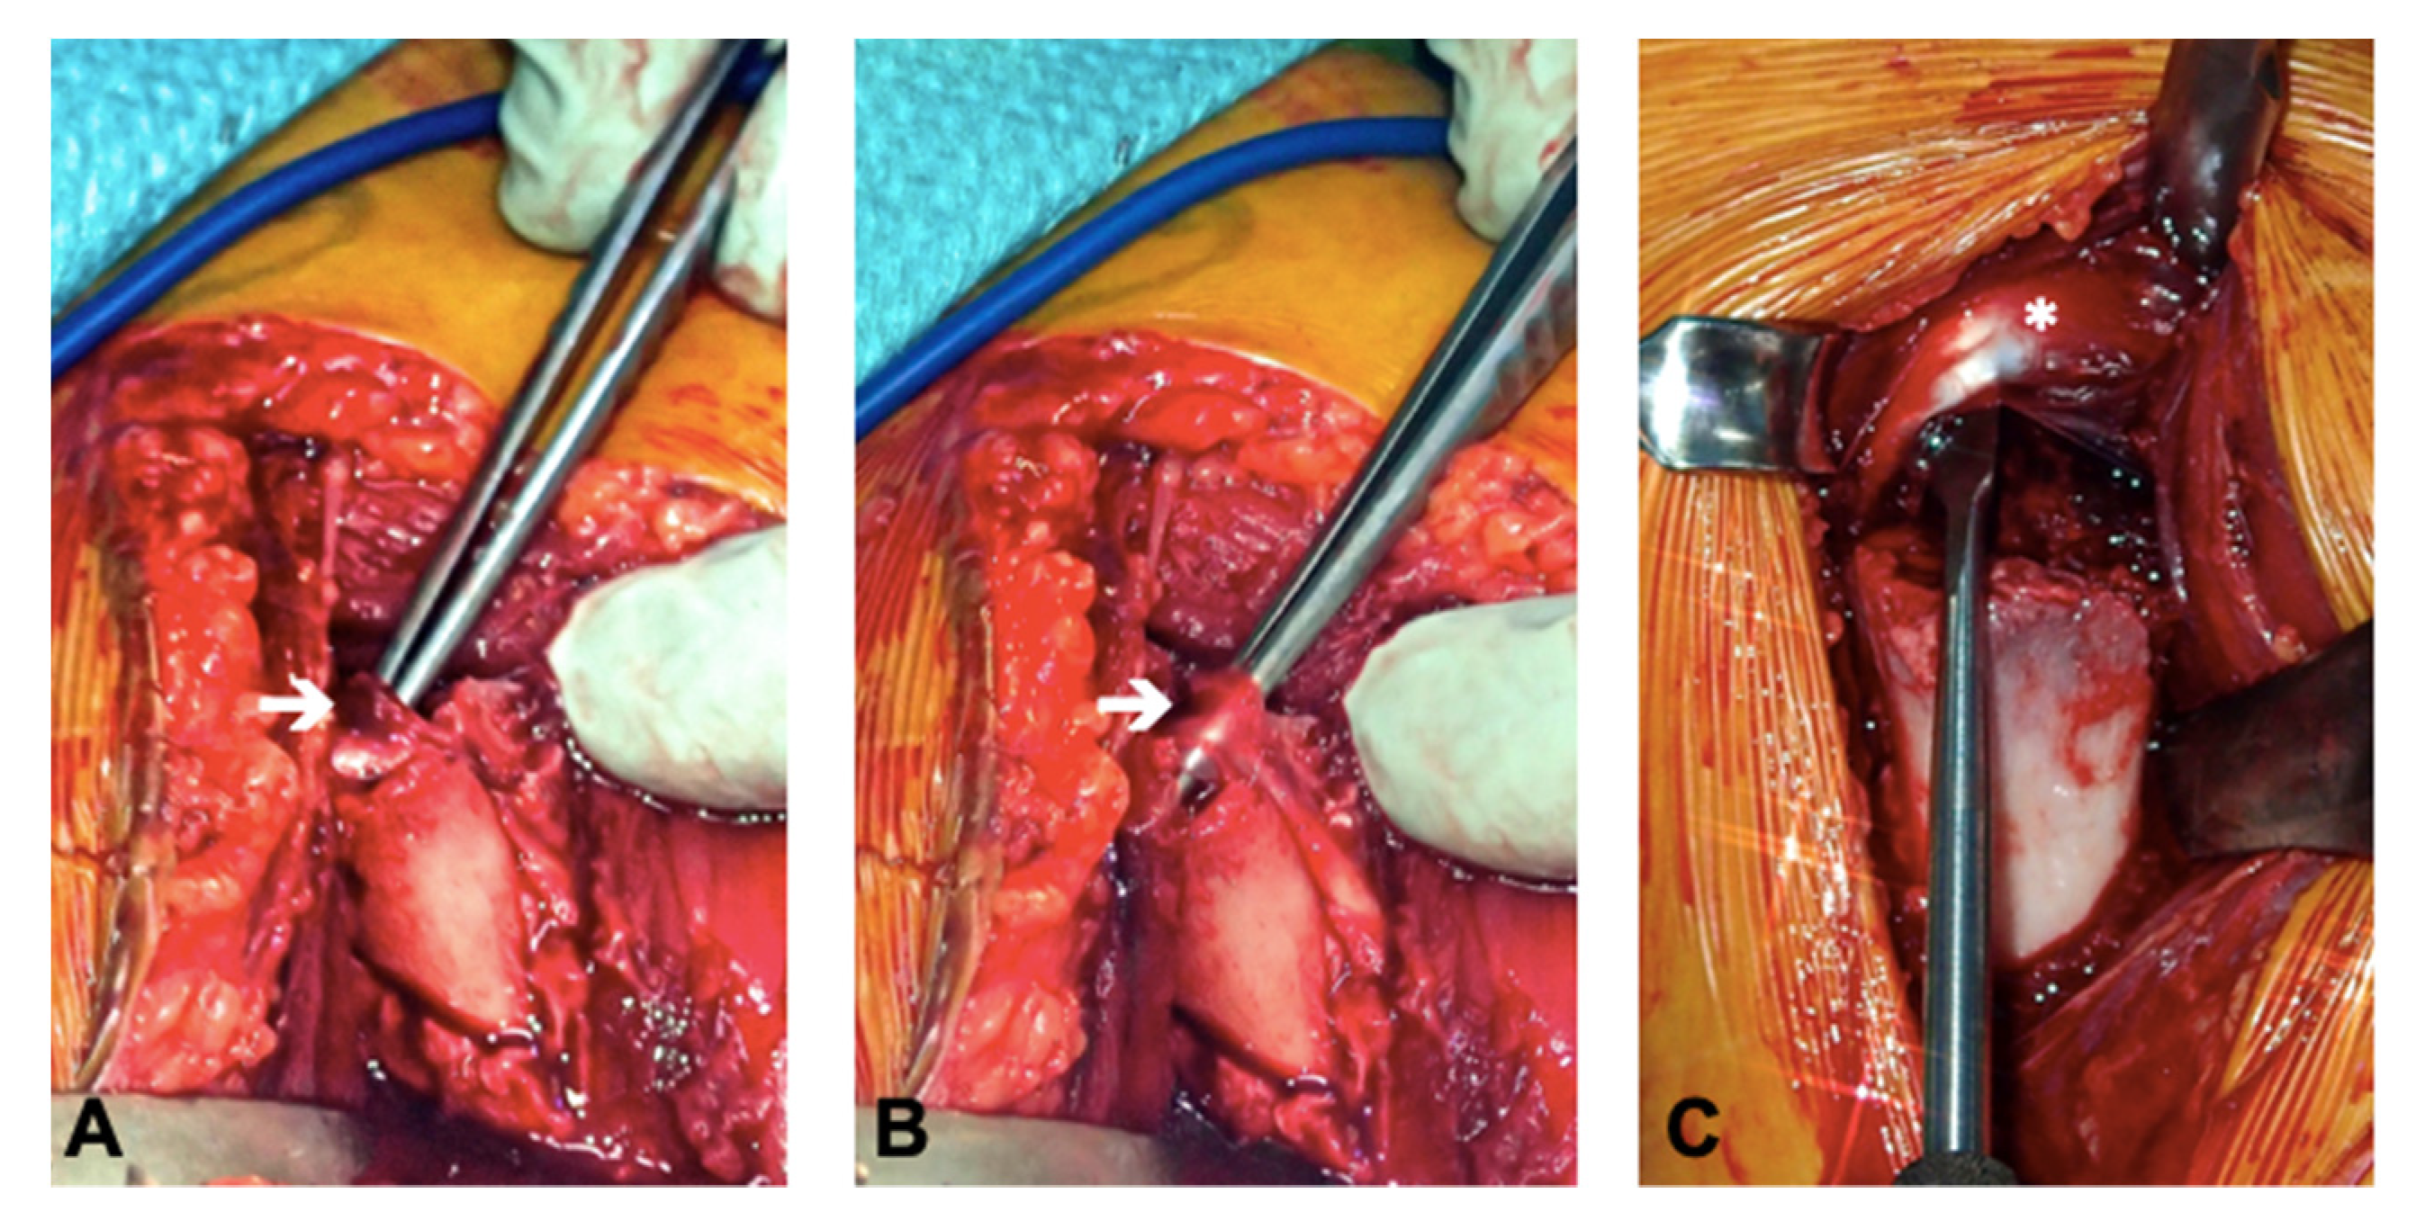

For this patient, it was apparent that a closed reduction was impossible due to the interposition of soft tissue at the fracture site. Tissue entrapment was intraoperatively observed in all of the six cases (the long biceps tendon in two cases (Pat. N° 1 and 5), periosteal tissue in two cases (Pat. N° 3 and 6), a bony fragment in one case (Pat. N° 4), and both the long biceps tendon as well as the conjoint tendon in one case (Pat. N° 4)) (

Figure 3).

Two years postoperatively, we were able to demonstrate excellent shoulder function and preserved anatomical integrity of the entrapped tissues, namely, the biceps and conjoint tendon. To the best of our knowledge, this is the first report on the integrity of the interposed structures. It might well be questioned, whether these structures would have been intact, if a closed reduction had been accepted.

The first patient of this series (

Figure 2) was initially treated with a closed reduction and percutaneous pinning. Due to secondary displacement, a revision with an open reduction and internal fixation was necessary caused by a biceps entrapment. Subsequently, we treated unreducible fractures by an open reduction and internal plate fixation and found tissue entrapment to be present in all cases.

Figure 5). The obstacle to reduction was, in most cases, the entrapped biceps tendon. In one case, the entrapped conjoint tendons inhibited reduction and in one other case periosteal tissue.

In contrast, Bahrs et al. described open reduction in Neer III and IV fractures in 17 of their 31 patients. They found that in nine of these patients, the biceps tendon was entrapped in the fracture site. They concluded that a failed closed reduction should be interpreted as a possible soft tissue entrapment (most likely biceps tendon) and that these cases should be addressed with an open reduction and the removal of the entrapped structures [

14].

Performing an open reduction, we could liberate the tissue interposed in the fracture side and achieve an anatomical reduction. To achieve a stable fixation of our reduction without crossing the physeal plate, we decided to use a T-plate fixation.